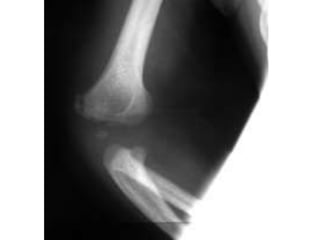

TNA

Fratura recente sobre

calo antigo.

Ulna esquerda.

Murray, 2008

TNA Fratura recente sobre caloantigo. Ulna esquerda. Murray, 2008